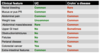

Compare UC and CD with the following:

a) rectal bleeding

b) mucus/pus PR

c) abdo pain

d) wt loss

e) abdo mass/abscess

f) upper GI tract

g) obstruction/strictures

h) fistulas

i) perianal disease

j) colorectal cancer

k) extra-intestinal features

[Table]

UC don’t tend to get progressively worse unlike Crohn’s